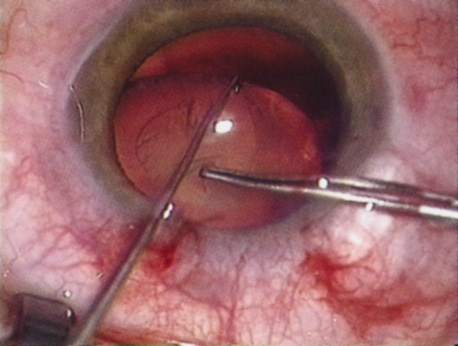

Capsulorrhexis can be performed with a cystitome, capsulorrhexis forceps, or combination-type instruments. Regardless of which instrument is used, several principles can help the surgeon successfully complete capsulorrhexis. It is important to maintain the anterior chamber, because making the chamber shallow increases tension on the zonules and causes the tear to run peripherally. The authors recommend the use of a viscoelastic agent for maintaining chamber depth and, of course, for endothelial protection. Therefore, if the tear begins to run peripherally, the surgeon should redeepen the anterior chamber before attempting to redirect the tear. Additionally, folding the capsule margin can aid the surgeon in redirecting the tear more accurately (Fig. 10).

Fig. 10. The capsulorrhexis tear is more easily redirected by folding the capsule over, in advance of the tear.